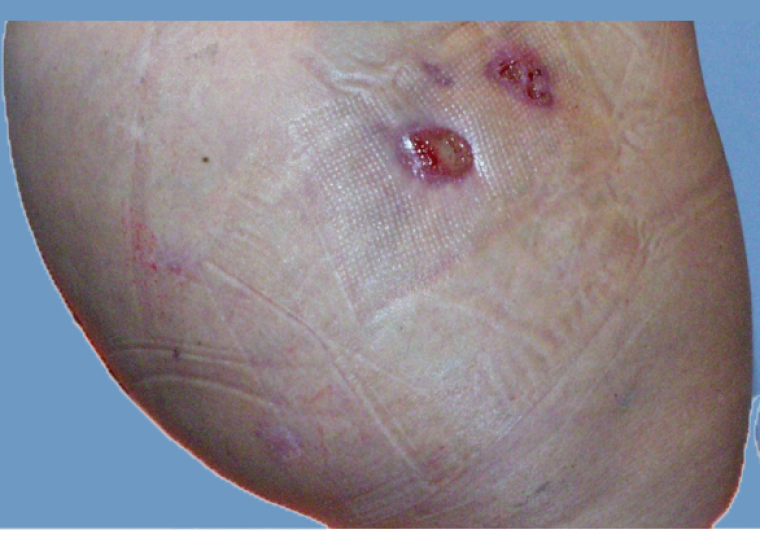

Mesotherapy is ineffective and lead to more ecchymosis than Endopeel .A comparative study shows that with Endopeel you get a great projection of the butts with a lifting too of the infra gluteal fold ( banana fold).

In such case, endopeel is great to perform at least 3 months after fat grafting to get a nice 3d shape.